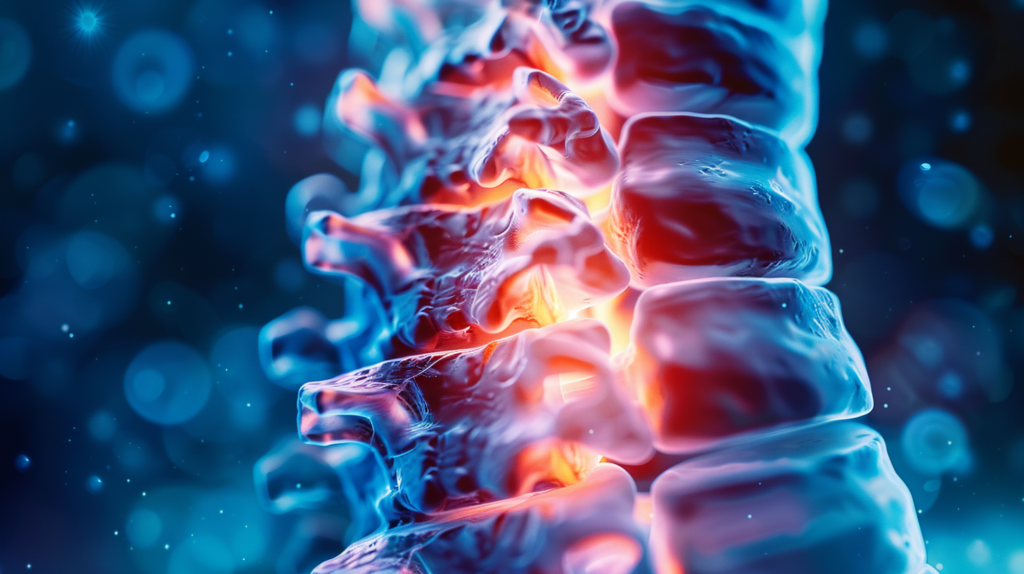

Остеохондроз поясничного отдела – это дегенеративное заболевание позвоночника, при котором происходят изменения в межпозвонковых дисках и окружающих тканях. Проще говоря, это процесс “изнашивания” нашего позвоночника, который чаще всего затрагивает именно поясничный отдел.

Почему именно поясница? Дело в том, что поясничный отдел несет на себе основную нагрузку при движении и поддержании веса тела. Представьте себе, что ваш позвоночник – это башня из кубиков. Нижние кубики (поясничный отдел) несут на себе вес всей конструкции, поэтому они и “изнашиваются” быстрее всего.

При остеохондрозе межпозвонковые диски, которые служат своеобразными амортизаторами между позвонками, теряют свою эластичность и высоту. Они становятся более плоскими и менее способными выполнять свою функцию. Это приводит к тому, что позвонки начинают сближаться, что может вызывать дискомфорт и боль.

Но на этом процесс не останавливается. Организм, пытаясь компенсировать эти изменения, начинает формировать костные разрастания – остеофиты. Эти костные шипы могут сдавливать нервные корешки, что приводит к еще большей боли и нарушению функций.

Особое внимание стоит уделить нервным корешкам, которые выходят из спинного мозга через отверстия между позвонками. Именно сдавливание этих корешков при остеохондрозе часто является причиной острой боли и нарушения функций.

Из-за уменьшения высоты дисков и образования остеофитов нервные корешки могут оказаться зажатыми.

При прогрессировании остеохондроза, фиброзное кольцо диска может разорваться, и его содержимое выпячивается наружу. Это может вызвать сильную боль и неврологические симптомы.

Сужение позвоночного канала может привести к сдавливанию нервных корешков или спинного мозга, вызывая боль, онемение и слабость в ногах.

Сдавливание нервных корешков может вызвать острую боль, которая распространяется вдоль пораженного нерва, часто сопровождаясь онемением и мышечной слабостью.

Это редкое, но серьезное осложнение, возникающее при сдавливании нервных корешков в нижней части позвоночника. Оно может привести к нарушению функций тазовых органов и требует экстренного хирургического вмешательства.